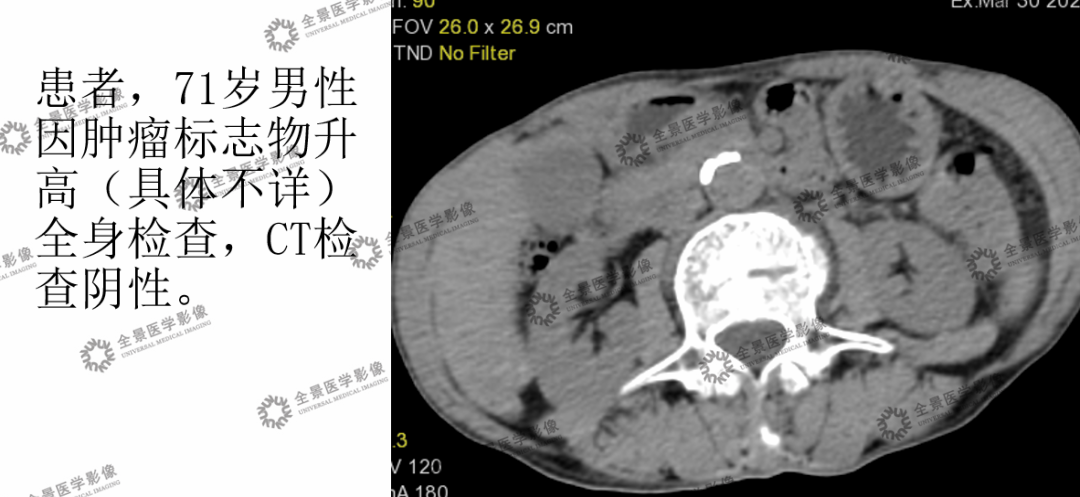

(2)肿瘤标志物升高查原因